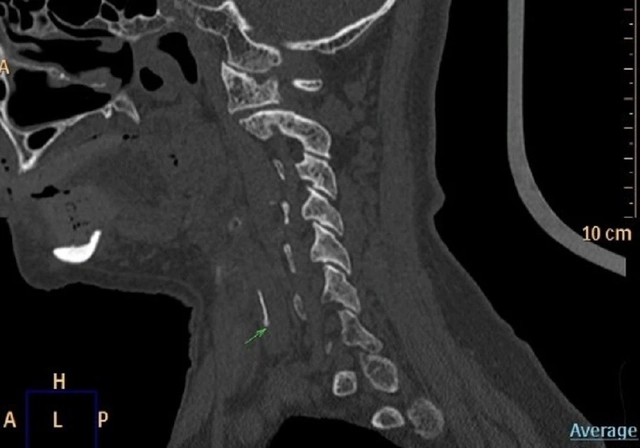

Khi đến bệnh viện, người bệnh trong tình trạng đau họng dữ dội, nuốt rất khó và bắt đầu xuất hiện khó thở. Nội soi thanh quản cho thấy sụn thanh thiệt và sụn phễu phù nề nghiêm trọng, mất rãnh lưỡi – thanh thiệt, che lấp gần như toàn bộ đường thở. Chụp CT xác định tình trạng phù nề nặng ở thanh thiệt, sụn phễu và đáy lưỡi, nguy cơ tắc nghẽn đường thở rất cao, có thể đe dọa tính mạng nếu không xử trí kịp thời.

Dị vật đường tiêu hóa là tình huống thường gặp nhưng đặc biệt nguy hiểm nếu không được can thiệp sớm

Bệnh nhân được chỉ định nhập viện ngay lập tức để theo dõi và điều trị tích cực. Sau khi nội soi lấy dị vật kết hợp kháng sinh, kháng viêm, phun khí dung và giảm đau, tình trạng phù nề giảm dần, các triệu chứng của người bệnh hiện đã cải thiện rõ rệt.